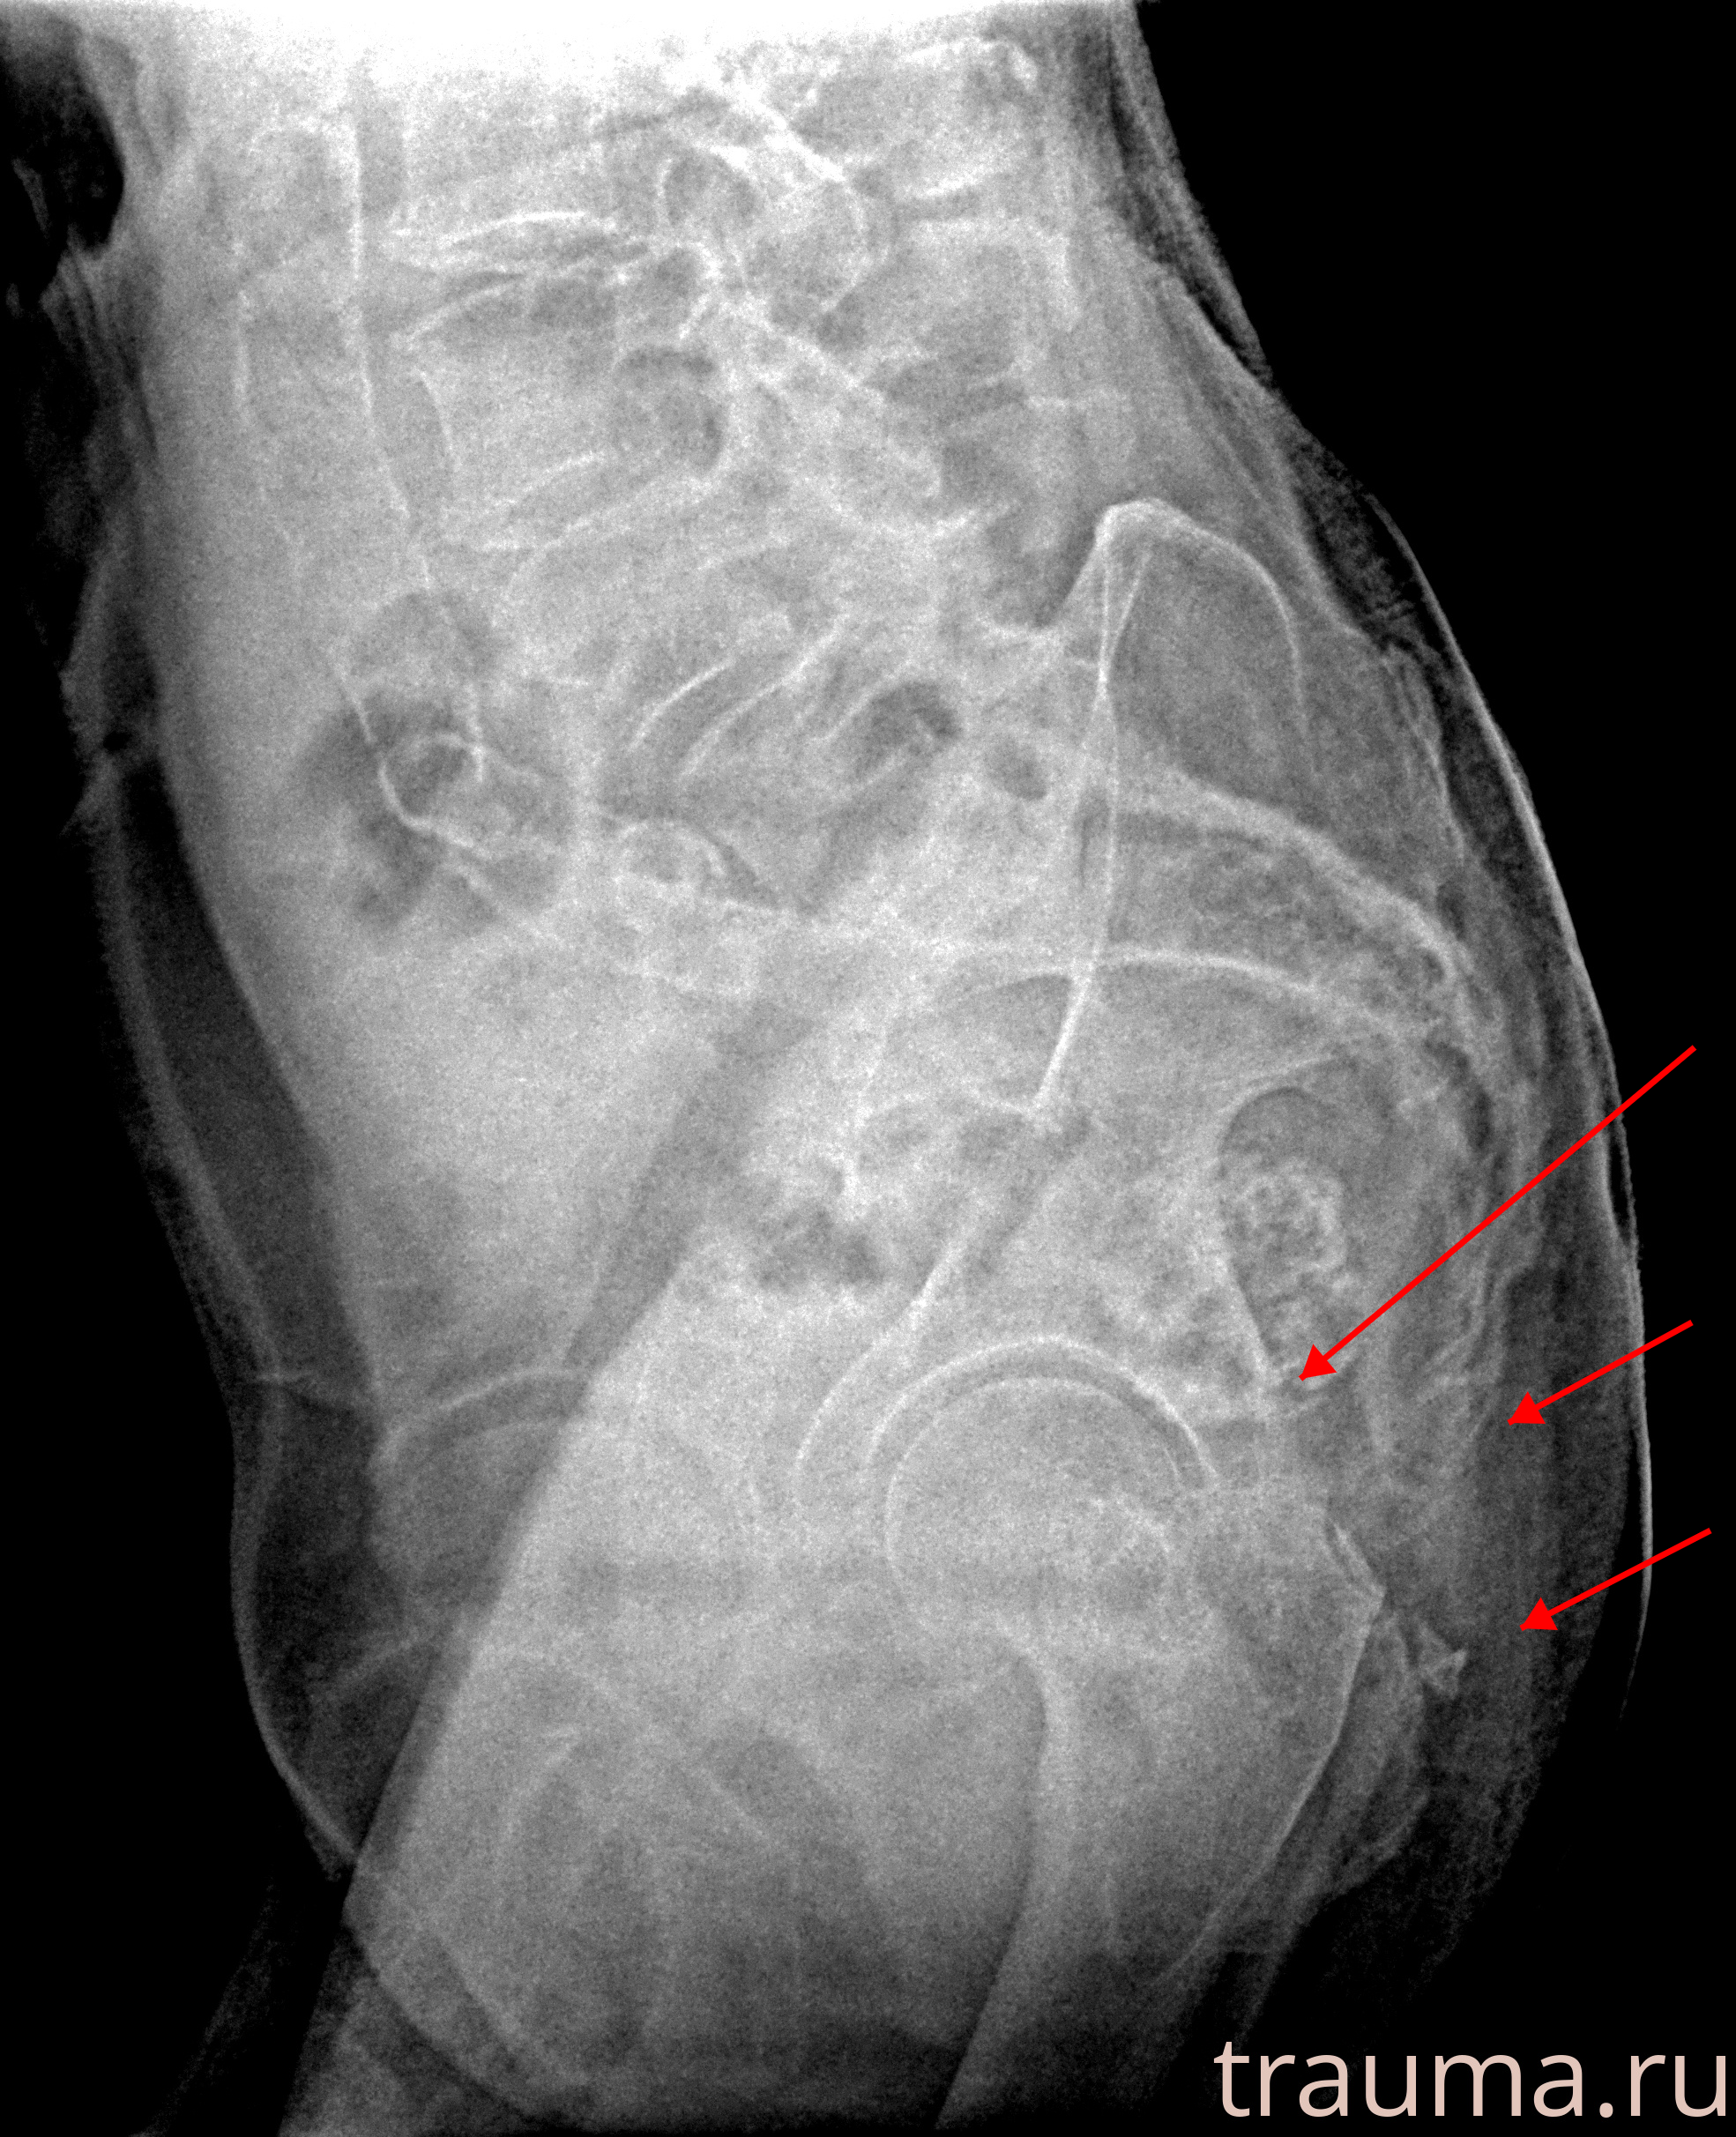

Рентгенограммы

Рентген на дому: по вашему адресу приезжает врач-рентгенолог, травматолог-ортопед с мобильным рентгеновским аппаратом, проводит диагностику травмы или заболевания, делает необходимые рентгенограммы, дает рекомендации по дальнейшему лечению. Получить качественные снимки в домашних условиях возможно благодаря уникальной методике, разработанной МосРентген Центром для института  Склифосовского

при переломе шейки бедра и пневмонии от компании МосРентген Центр - партнера Института имени Склифосовского